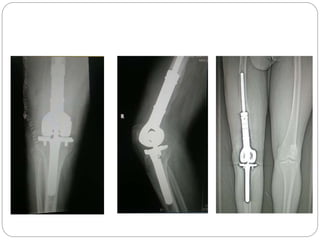

This document discusses 8 oncology cases. Case 1 involves a 40-year old female with right knee pain. Case 2 is a 28-year old male with a left subtrochantric fracture from a MVA who is now experiencing increasing left knee pain and swelling. Biopsy results showed high-grade osteosarcoma. Case 3 is a 30-year old female with breast cancer and bone metastases causing bilateral hip pain.